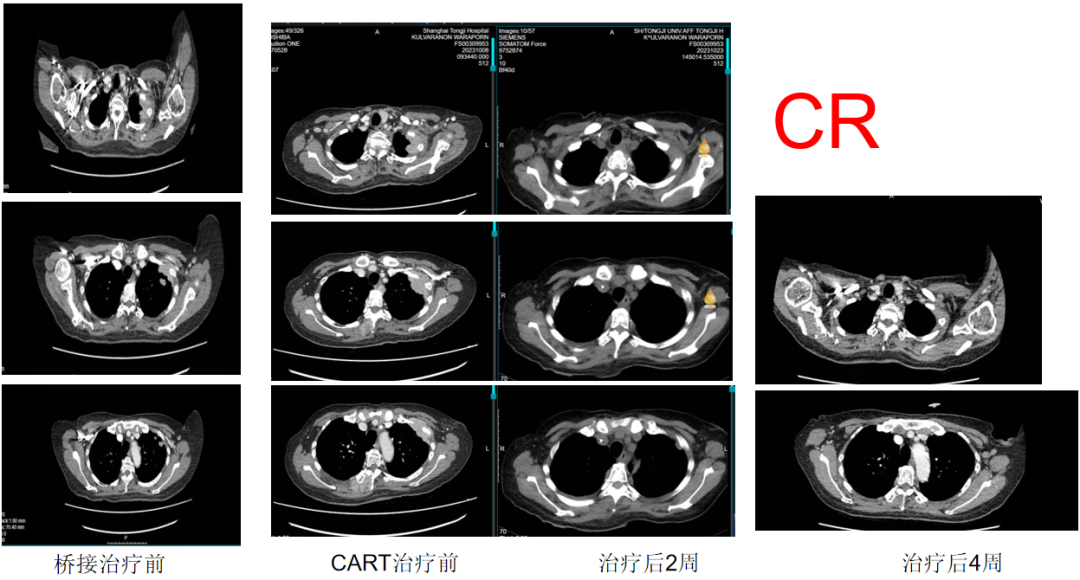

当所有的治疗方案已经用尽,癌症迅速进展,医生遗憾的说,M女士对任何药物都没有反应,这种情况只能进入最后的临终关怀,这意味着M女士没有机会再与这种疾病作斗争了,她的生命进入了倒计时。幸运的是,M女士的家人在中国找到了全新的希望--CAR-T疗法。M女士在家人的陪伴下来到中国,在上海市同济医院接受全人源BCMA CAR-T治疗后仅22天,全身肿瘤奇迹消失,评效达到完全缓解(CR),M女士重获新生!

2023年9月,在详细的了解病情并做了完善的检查后,李教授约了多位权威专家共同讨论,最终认为个体化BCMA CAR-T治疗方案获益最大。